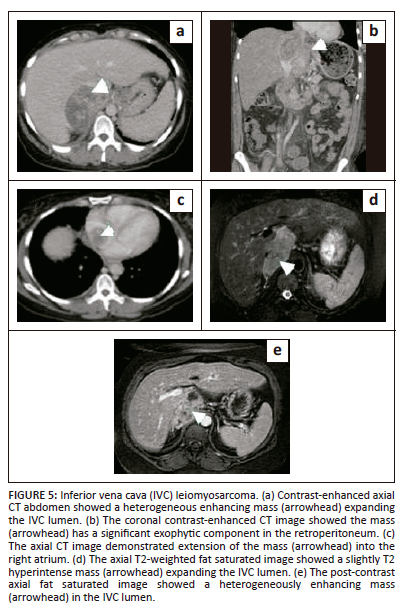

Primary inferior vena cava leiomyosarcoma

This is an uncommon malignancy, accounting for less than 1% of all malignancies. Yet, it is the most common primary malignancy involving the IVC.22 Nearly three-quarters of these tumours arising from large veins are leiomyosarcomas.2 These tumours originate from the smooth muscle cells of the vessel wall. Nearly three quarter of these cases occur in middle-aged women.23 Most leiomyosarcomas are large at presentation. They present with non-specific symptoms such as abdominal pain, a palpable mass and lower limb oedema. Inferior vena cava leiomyosarcoma initially has intramural growth, but ultimately two-thirds have extraluminal growth.24,25 Intraluminal growth causes venous obstruction while extraluminal growth results in invasion of adjacent structures. Involvement of the renal and suprarenal IVC is seen in nearly half of the patients, and is associated with a better prognosis, while intrahepatic IVC involvement seen in less than 20% of cases, is associated with a worse prognosis.2 On imaging, it appears as a mass filling the IVC with heterogeneous enhancement. Non-enhancing areas within the mass represent necrosis (Figure 5). En bloc resection of the IVC and grafting is often performed as complete surgical resection is necessary for cure. The overall outcome is poor with a 14% 10-year survival rate and 50% recurrence.1,2